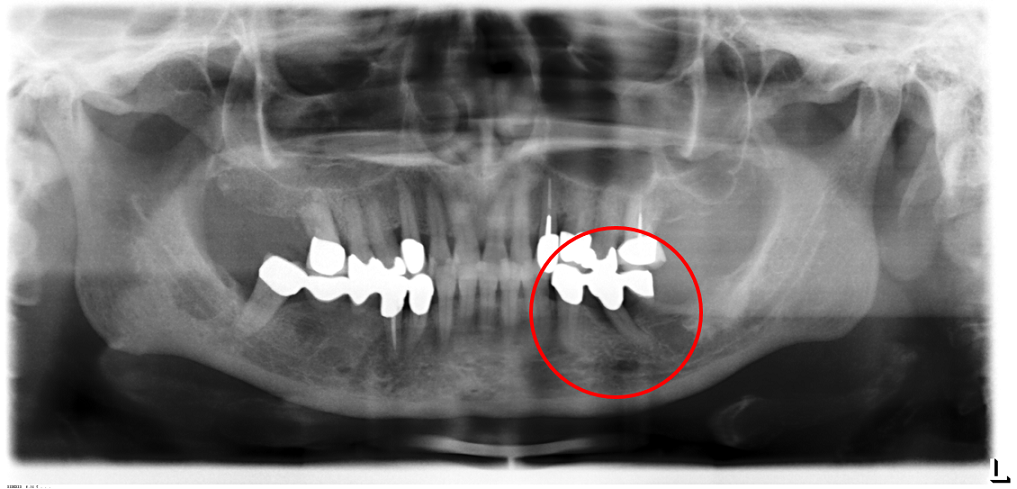

02/02 - Radiographic presentation of the defect 4 years following regenerative periodontal therapy with Straumann® Emdogain®. The radiograph demonstrated a complete defect fill and stable results.Contained intrabony defect treated using Straumann® Emdogain® - Prof. Dr. Dr. A. Kasaj